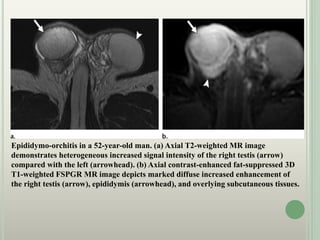

Epididymo-orchitis in a 52-year-old man. (a) Axial T2-weighted MR image

demonstrates heterogeneous increased signal intensity of the right testis (arrow)

compared with the left (arrowhead). (b) Axial contrast-enhanced fat-suppressed 3D

T1-weighted FSPGR MR image depicts marked diffuse increased enhancement of

the right testis (arrow), epididymis (arrowhead), and overlying subcutaneous tissues.